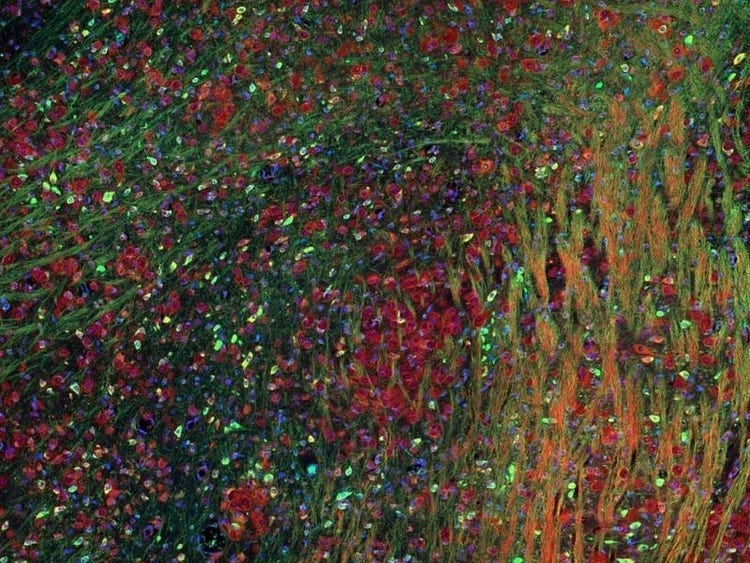

Fluorescence imaging of a mouse brain

Aunque todas estas imágenes parecen distintas en un primer plano, todas componen una única imagen de un cerebro de ratón capturada con el procesamiento de imágenes por fluorescencia.

El científico británico Sir George G. Stokes observó por primera vez que la fluorita mineral mostraba fluorescencia al iluminarla con luz ultravioleta y acuñó la palabra "fluorescencia". Stokes descubrió que la luz de fluorescencia tiene longitudes de onda más largas que la luz de excitación, un fenómeno conocido como cambio de Stokes. La microscopía por fluorescencia es un método excelente para estudiar materiales que pueden fluorecer en su forma natural (calificado como primaria o autofluorescencia) o cuando se tratan con químicos que puedan fluorecer (conocido como fluorescencia secundaria).